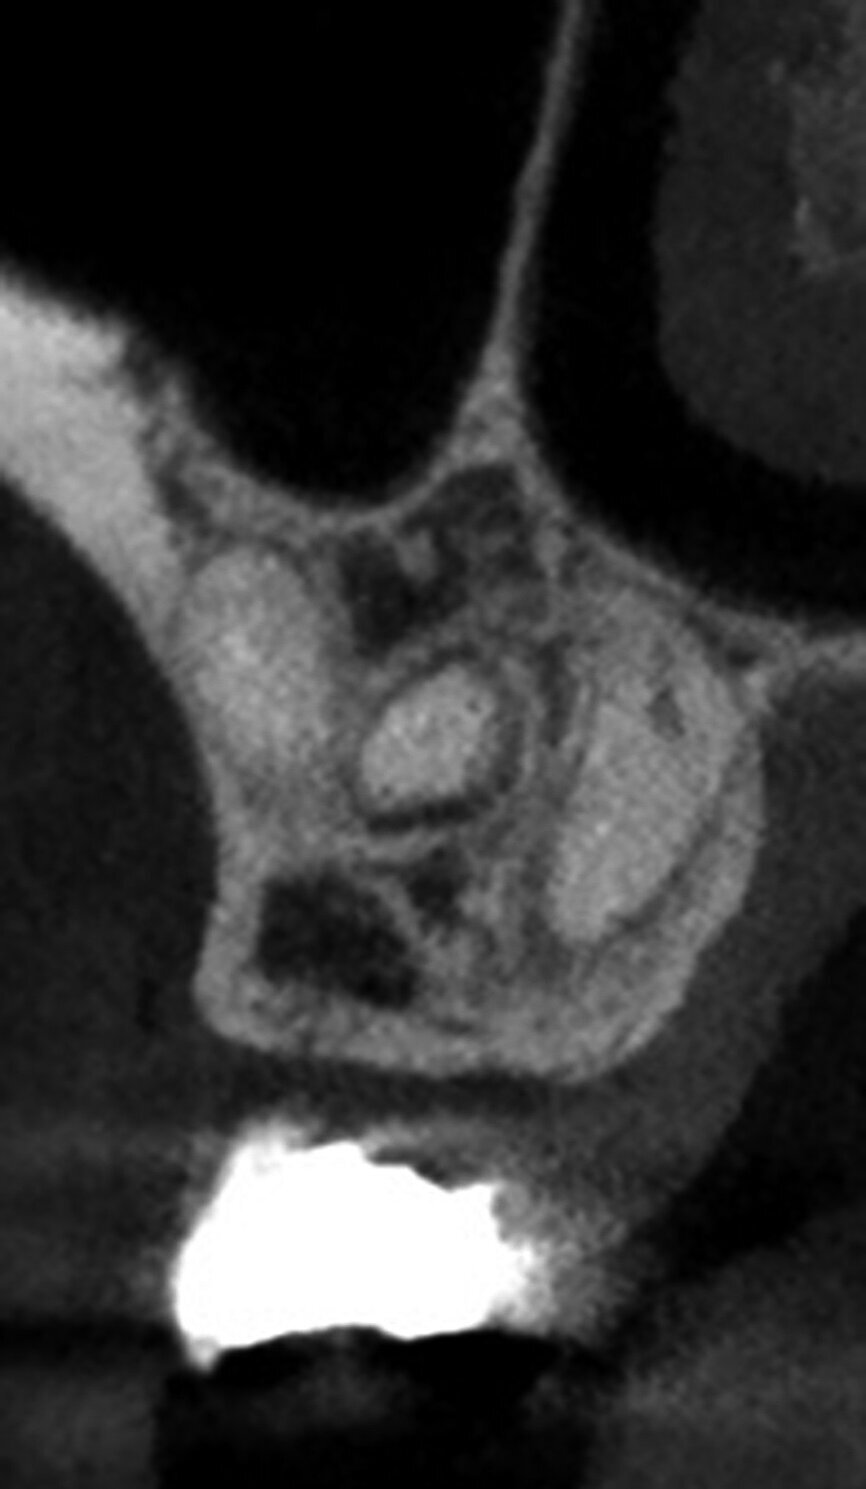

The second step, ‘3D Tooth Anatomy’, involved selecting the tooth to be examined and the entire volume was cropped to only leave the data of interest behind (Fig. 5). In the third step, ‘Canal System’, the number of root canals were identified and each root canal was then mapped separately by identifying the orifice and radiographic apical foramen of each root canal (Fig. 6).

With the fourth step, ‘3D Canal Anatomy’, the software made a proposal of the canal anatomy (Fig. 7), but the operator can make corrections according to the canal configuration that can be viewed in different planes in the software. Figures 8 to 10 show the mapping of the palatal, mesiobuccal, and distobuccal root canal systems.

During the fifth step, ‘Treatment Plan’, the software projected ISO size 06 instruments into the canals (Fig. 11), which allowed the operator to visualise the internal anatomy of the canals, check straight line access, and modify the proposed access if necessary. A rubber stop on the files can then be digitally adjusted to a coronal reference point of choice that will then indicate the proposed working length for each root canal system. This view can also be rotated in 3-D to alert the operator of the angle and direction of curvatures in the root canal systems (Fig. 12). The step after ‘treatment plan’ is to select a master file from a preloaded database of endodontic file systems that will most likely result in optimal canal preparation for that specific shape or diameter of a canal. Considering the s-shaped curvatures in all three root canal systems as well as the sharp curvatures in different planes, it was decided to use the Primary WaveOne Gold file (25/07) in the palatal canal and the Small WaveOne Gold file (20/07) for root canal preparation in the two-challenging buccal root canal systems (Fig. 13). The selected instruments were then displayed in the root canal systems and the operator again digitally rotated and visualised the root canal anatomy in 3-D (Fig. 14).